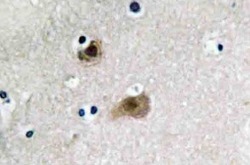

AP20452PU-N IHC

Full details

Method: